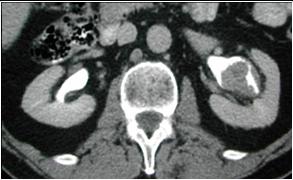

IV contrast shows tumor  in renal pelvis

Transitional cell Ca